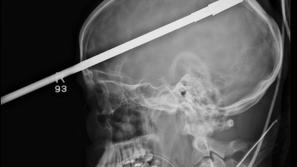

Glavo mu je preluknjala harpuna

Šestnajstletnik čudežno preživel strel v glavo s harpuno. Posledic ne bo imel.